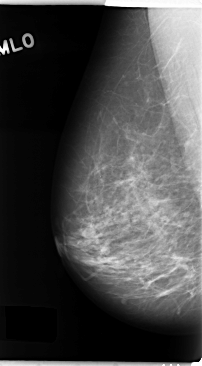

C_0137_1.RIGHT_CC

RIGHT_MLO LINES 4752 PIXELS_PER_LINE 2624 BITS_PER_PIXEL 12 RESOLUTION 50 NON_OVERLAY